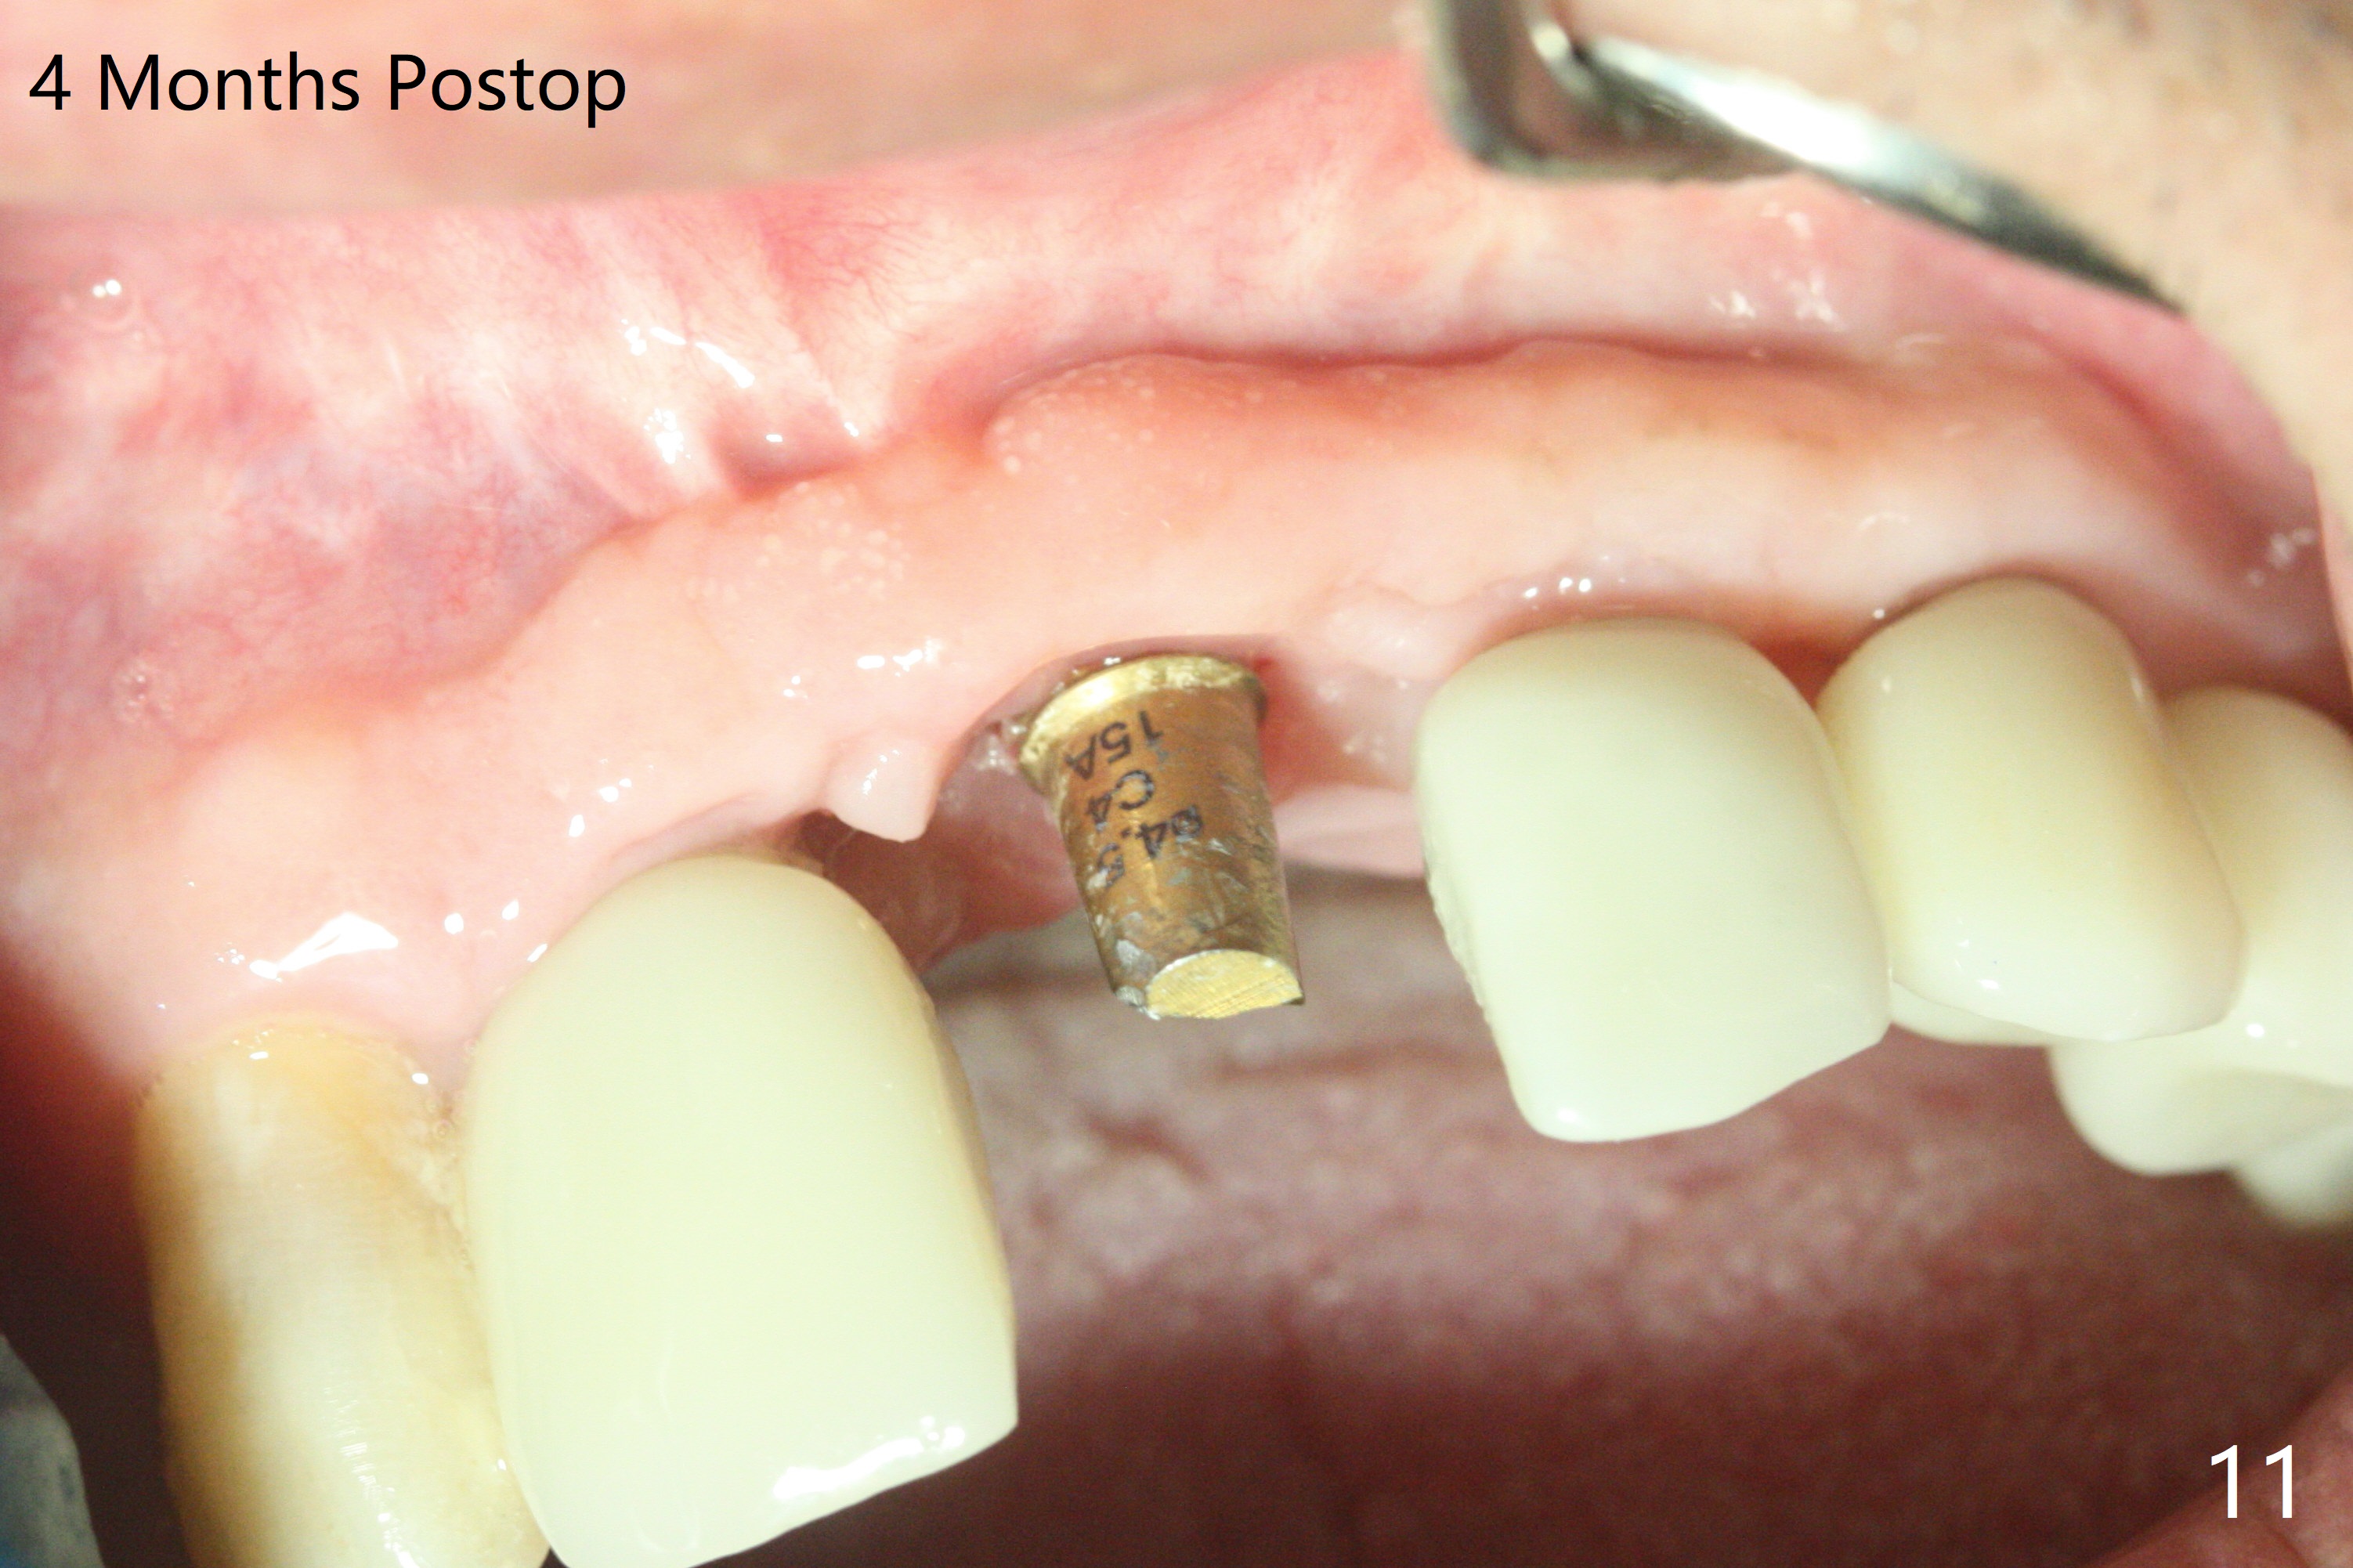

The implant access at #9 closes 1 week post implant fracture (Fig.1,4). There is mild gingival erythema at #10 (Fig.2,3 ^). There is bone around the fractured implant, which is palatally placed (Fig.5). The 2 mm implant is removed using 2/3 mm trephine bur. In spite of moving the osteotomy buccally, a 4.5x4 mm, 15 degree A-type angled abutment is installed for an immediate provisional following placement of a 3.5x10 mm implant (Fig.7, 25 Ncm). Sticky bone is placed (Fig.7 *) palatal to the implants at #9 and 10 (with thread exposure, Fig.6). While the majority of periodontal dressing remains in place (Fig.9,10), the suture in the exposed area appears to hold the papilla in place (Fig.8 <). Herpetic infection develops in the palate (Fig.9). Two months later, the gingiva at #10 is healthy; it appears that the implant threads are covered by bone graft. The immediate provisional (fabricated before suture) keeps the gingiva in an ideal position for impression of final restoration. It appears that the access hole is in a right area for screw retained restoration. The gingival cuff is healthy immediate pre-cementation, 4 months postop (Fig.12,13). The lab does not make access hole for the final crown (Fig.14). The implant remains subcrestal 4 months postop (Fig.15). Since the shade of the crown is off, the abutment remains un-torqued and the crown is cemented with temp bond. The implant threads at #10 seem to be covered by bone graft 4 months postop (Fig.16).